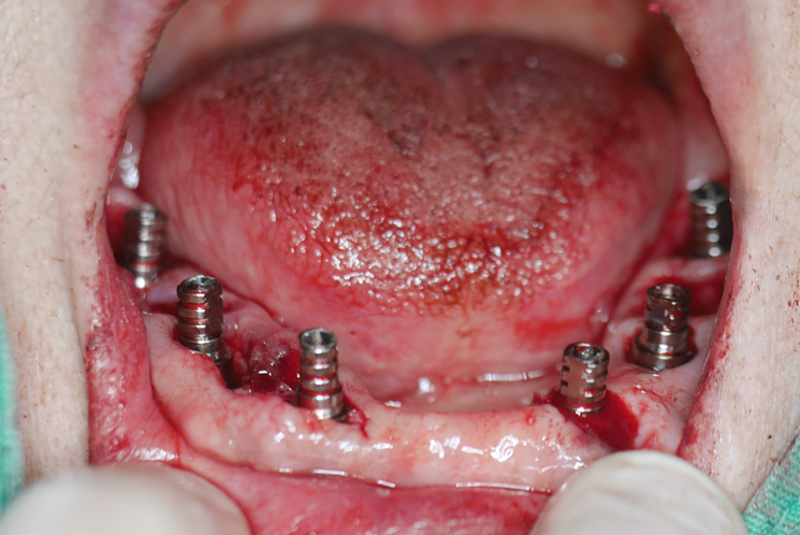

微創拔除蛀空殘牙:拔除已無保留價值的蛀蝕牙齒。

即刻補骨植牙: 在拔牙區域(或適當位置),利用先進的導引技術,無需大面積翻開牙齦(不翻瓣術式),精準植入多顆人工牙根(植體),作為新牙齒的穩固根基。同時進行必要的骨粉填補,確保植體長期穩定。

即刻安裝臨時固定假牙: 利用先進的CAD/CAM技術或預成連接件,在植體植入當天,立刻為張阿姨裝上一副堅固耐用的臨時固定假牙。這意味著張阿姨在離開診所時,嘴裡已經擁有了一副可以馬上使用的固定牙齒!